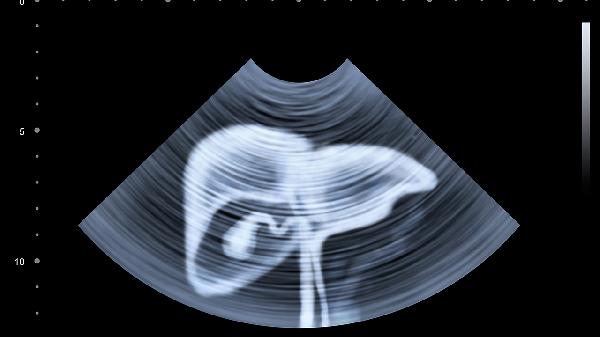

输尿管结石移动时可引发阵发性隐痛,可能放射至会阴部,伴随血尿或排尿困难。需通过超声检查确诊,较小结石可遵医嘱服用排石颗粒,疼痛明显时使用消旋山莨菪碱片解痉。

女性可能出现卵巢囊肿或子宫内膜异位症,表现为周期性下腹痛,经期加重。超声检查可明确诊断,遵医嘱使用散结镇痛胶囊缓解症状,必要时需手术干预。